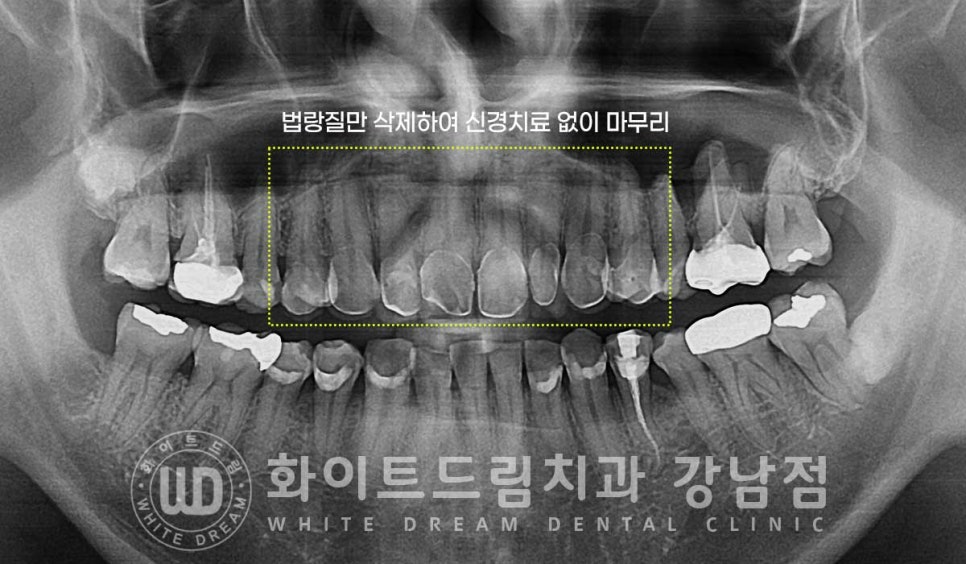

라미네이트 치료 시 치아를 과도하게 삭제하면

법랑질 내부 상아질과 신경이 노출되어 신경치료를 동반하게 되는 경우가 있습니다.

환자분은 틀어짐이 심해서 치아 삭제와 시린 증상에 대한 두려움이 크셨는데

본원의 라미네이트 노하우로 법랑질만을 살짝 다듬은 후 치료를 진행하여

신경치료 없이 치료를 마무리하게 되었답니다.